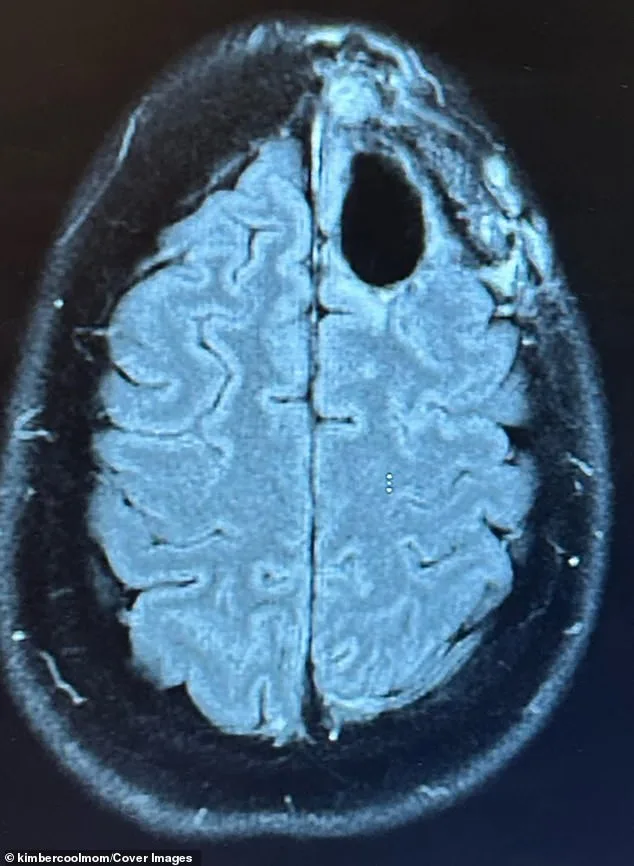

In August 2022, an MRI revealed a lime-sized mass in Pelling's frontal lobe. A biopsy confirmed her diagnosis, a cancer with a median survival rate of about 31 months. A former teacher and avid runner, Pelling believed she had done everything right. Yet the tumor, relentless and unyielding, seemed to defy all odds. She endured the standard treatments for aggressive cancers: chemotherapy, radiation, and brain surgery. The regimen left her bedbound, battling hair loss, fatigue, and brain fog. Eight months later, the cancer had progressed, forming a new, inoperable tumor. Her prognosis was slashed from three years to one.

In 2025, a routine brain scan delivered news that stunned Pelling. No evidence of cancer. 'I walked into that appointment prepared for anything,' she said. 'Hearing there was no evidence of cancer felt surreal.' Yet she knows the cancer might return. Today, she runs, cares for her boys, and shares her journey online. 'Every extra day with my boys is a miracle to me,' she said. 'It's about showing up for my boys and my husband, Ed. It's about gratitude and faith.'